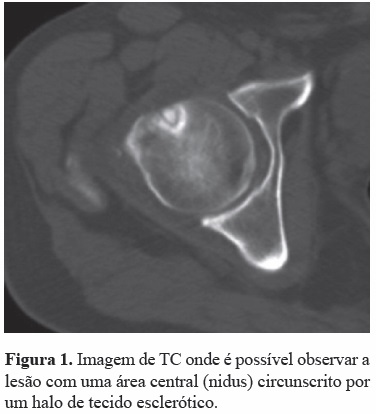

As radiografias não apresentavam qualquer alteração. A cintigrafia, a RM e sobretudo a TC revelaram uma lesão na porção anterior da transição cabeça-colo femoral compatível com osteoma osteoíde (Figura 1).

A entidade clínica designada osteoma osteoide foi descrita pela primeira vez por Jaffe[1-3] em 1935. É considerado um tumor ósseo benigno de pequenas dimensões que cursa frequentemente com dor intensa[2-7]. Esta lesão apresenta uma área central, o nidus, constituído essencialmente por tecido ósseo e osteoide circunscrito por um halo de tecido esclerótico[2-5].

Na maioria dos casos o exame de escolha numa fase inicial é a radiografia[1-5]. As lesões localizadas na cortical podem apresentar uma área arredondada de osteólise envolvida por um halo de tecido esclerótico[1,2,5]. Apesar da cintigrafia óssea apresentar elevada sensibilidade, não é considerada um método específico para determinar as características distintas destas lesões[2]. O papel da ressonância magnética (RM) é controverso, a literatura considera que a acuidade diagnóstica é inferior a tomografia computorizada (TC) na deteção do nidus e que a presença de edema ósseo associado a alterações das partes moles pode confundir o diagnóstico[2,3,12]. A TC é considerada o exame complementar de diagnóstico de eleição, sendo fundamental para caracterizar a correta posição anatómica do nidus e para ajudar no diagnóstico diferencial com outras entidades[2,3,12].